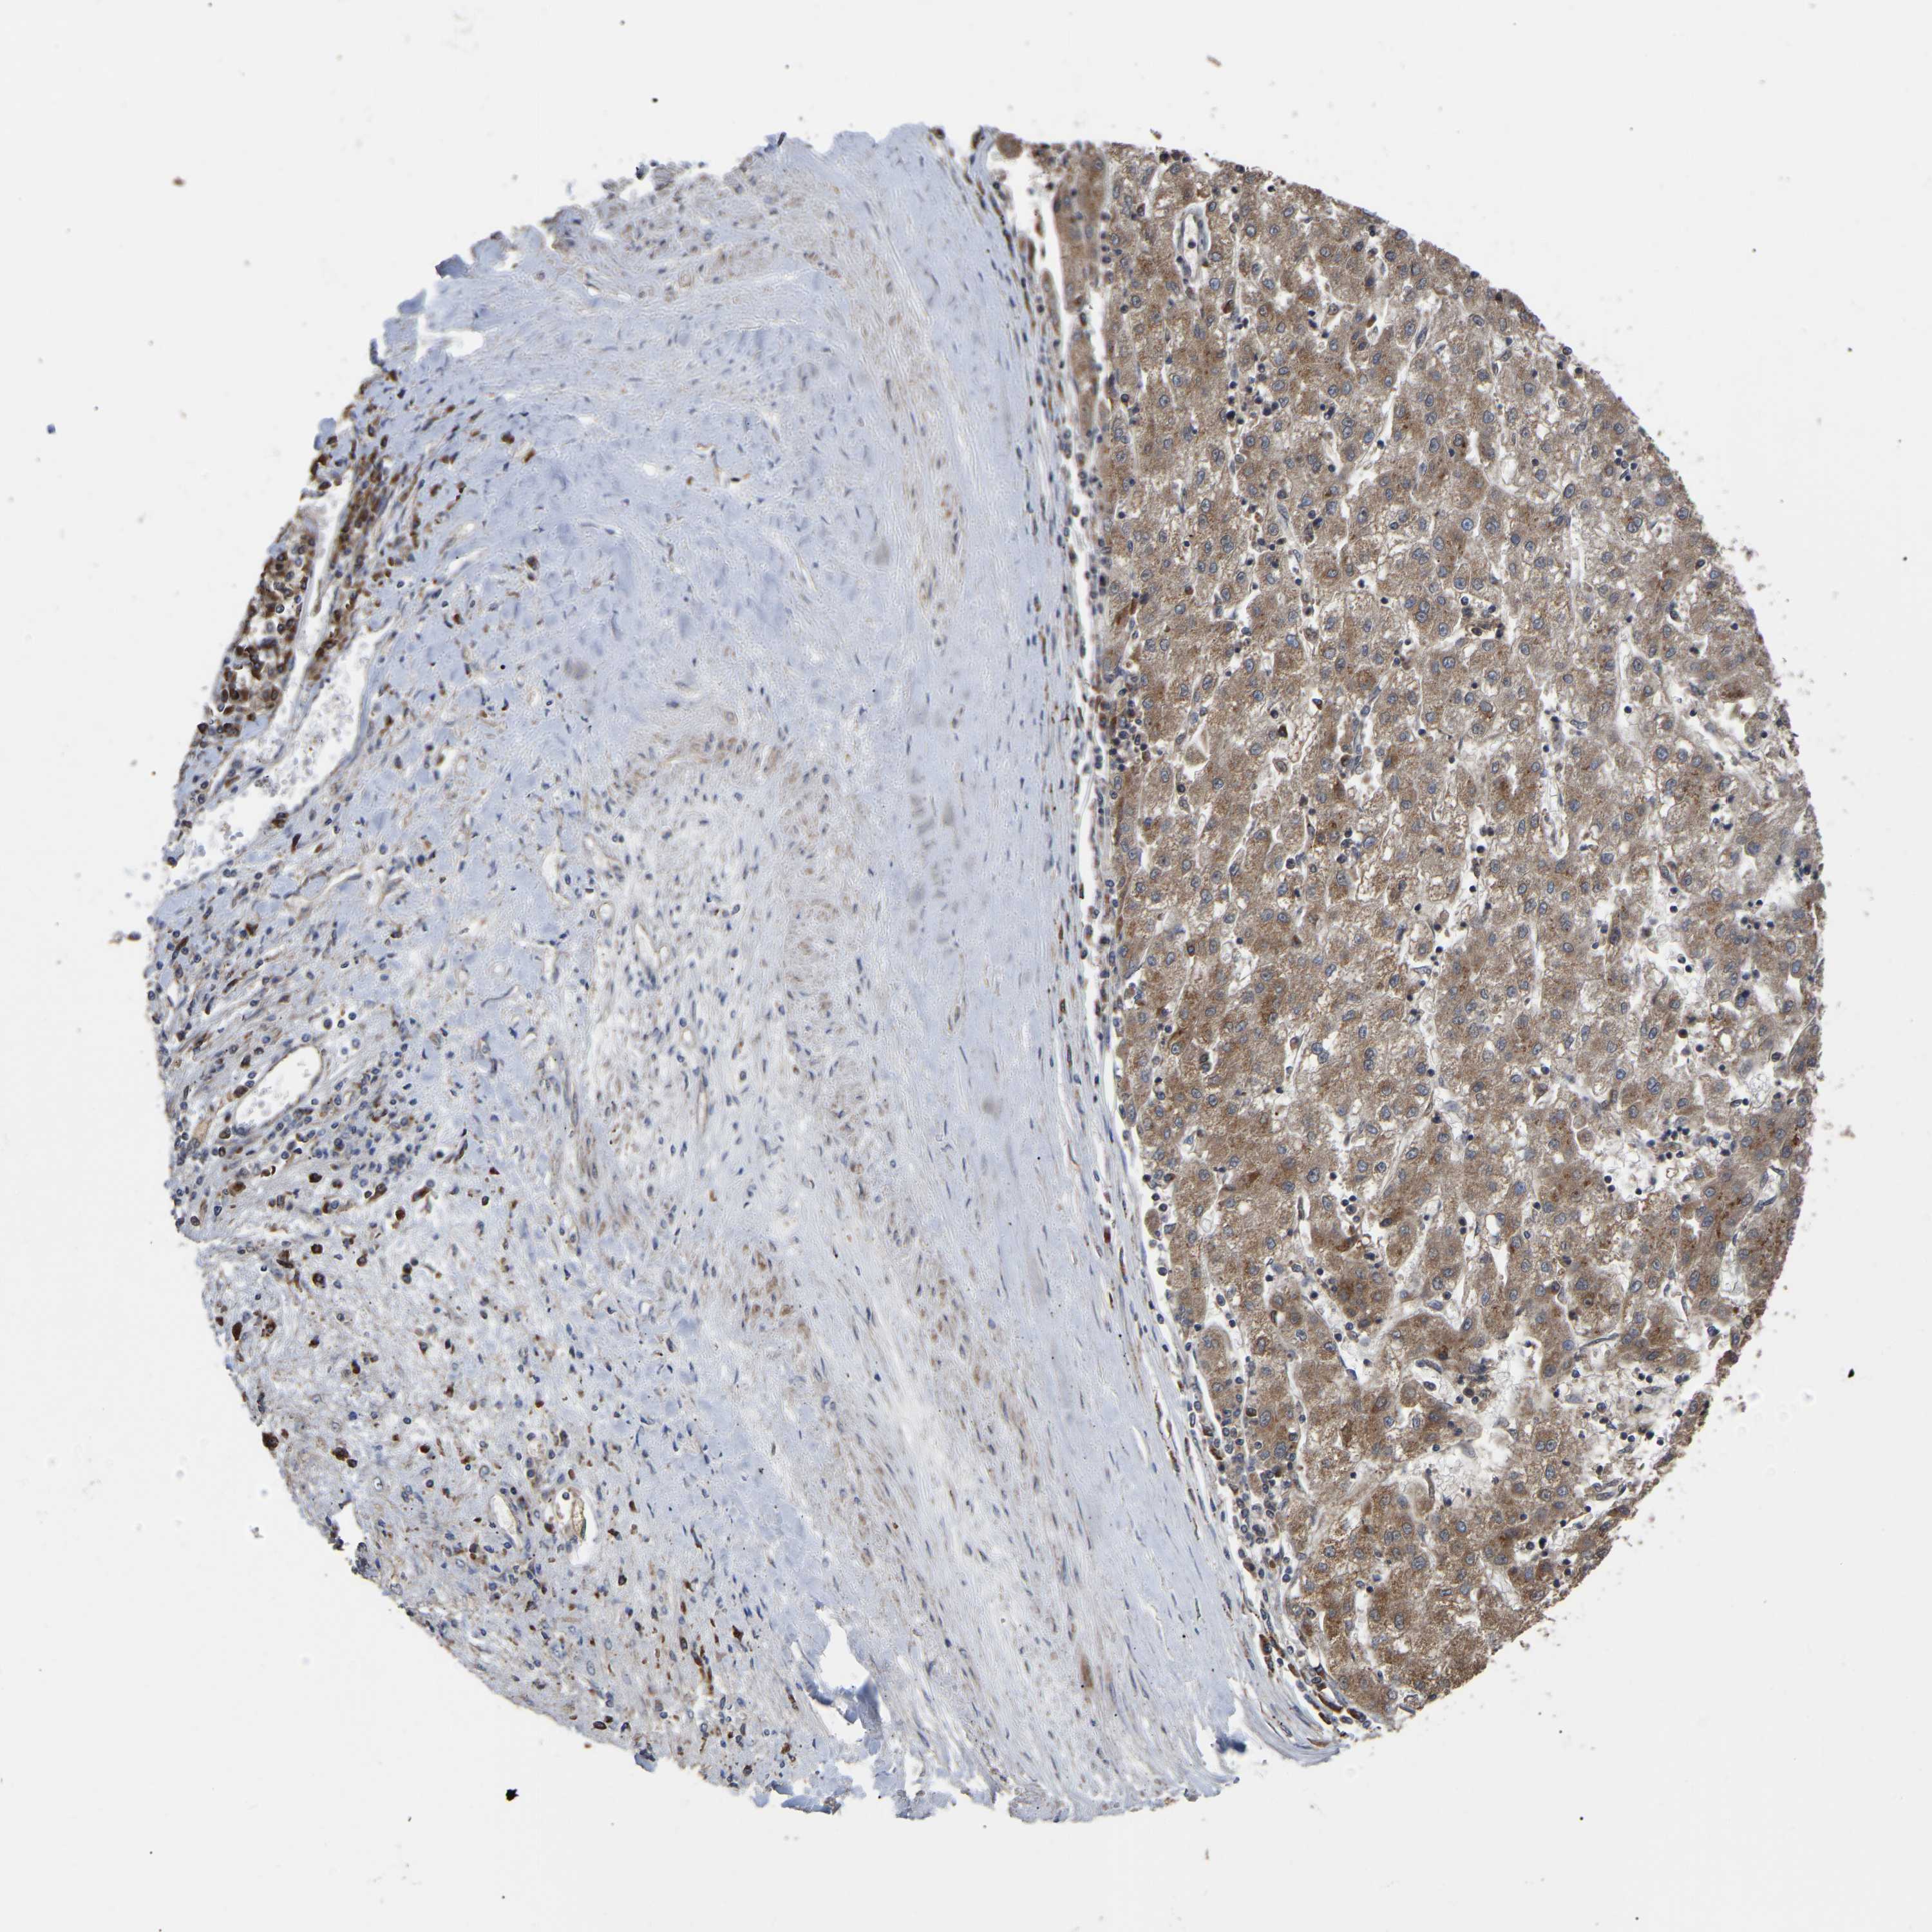

LIVER CANCER - Protein expressioni

A mouse-over function shows sample information and annotation data. Click on an image to view it in a full screen mode. Samples can be filtered based on level of antibody staining by selecting one or several of the following categories: high, medium, low and not detected. The assay and annotation is described here.

Antibody stainingi

Antibody staining in the annotated cell types in the current human tissue is reported as not detected, low, medium, or high, based on conventional immunohistochemistry profiling in selected tissues. This score is based on the combination of the staining intensity and fraction of stained cells.

Each image is clickable and will lead to virtual microscopy that enables deeper exploration of all samples and also displays staining intensity scores, fraction scores and subcellular localization as well as patient and tissue information for each sample.

Antibody HPA019369

Antibody HPA021323

Staining

High

Medium

Low

Not detected

Intensity

Strong

Moderate

Weak

Negative

Quantity

>75%

75%-25%

<25%

None

Location

Nuclear

Cytoplasmic/membranous

Cytoplasmic/membranous,nuclear

Cholangiocarcinoma

Carcinoma, Hepatocellular, NOS